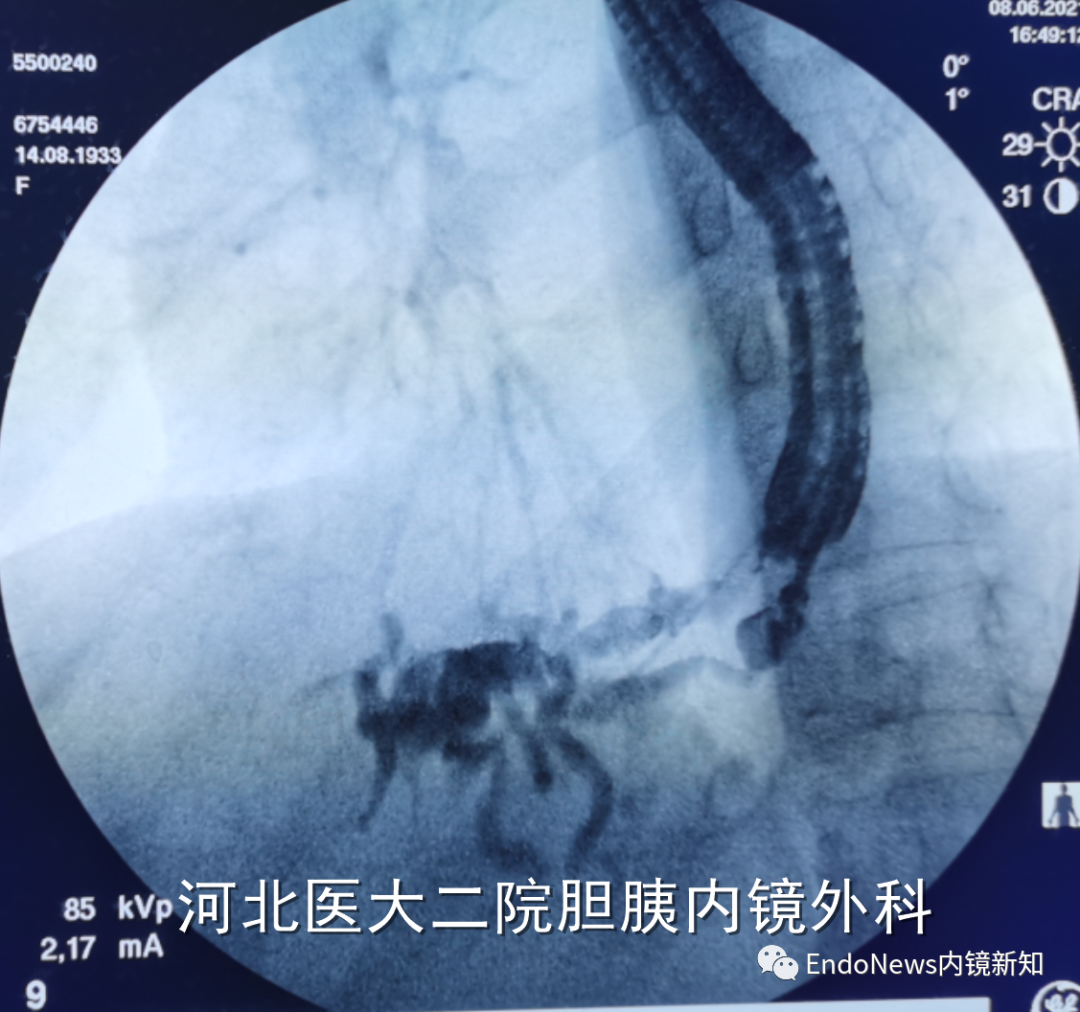

如下图所示,肝门胆管狭窄(Bismuth IV型),导丝进入肝右叶胆管后就可以置入支架引流肝右叶胆管:

取石网篮 为什么贵EUS-BD操作中的细节:导丝如何超选?_https://www.jmylbn.com_新闻资讯_第14张

取石网篮 为什么贵EUS-BD操作中的细节:导丝如何超选?_https://www.jmylbn.com_新闻资讯_第15张

在下面肝内胆管结石的病例所示,这是一个进肝右叶管之后顺行放置双猪尾支架,在二期手术时将窦道扩开,用字母镜液电碎石,再在右侧肝内胆管管进行取石的病例。